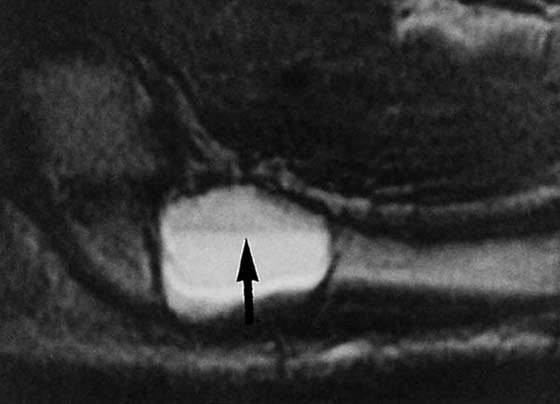

images

Figure 13-28 Magnetic resonance image demonstrating a scaphoid fracture (disruption in the black cortical line at the thin arrow). The marrow of the scaphoid is relatively darker (thick arrow), indicating edema from the fracture.